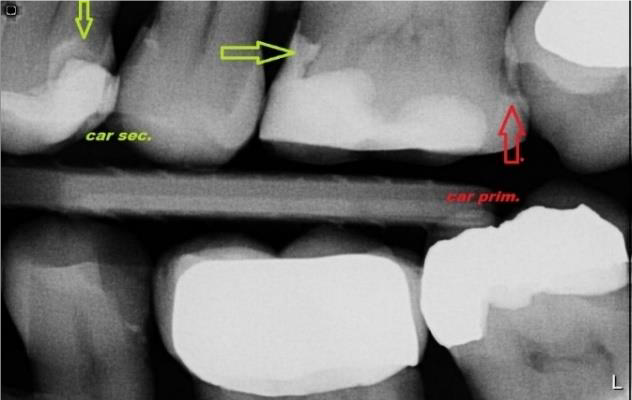

Der neue Patient wird zunächst zur Erstuntersuchung bestellt. Während des ersten Besuchs untersuchen wir den Zustand Ihrer Mundhöhle, Ihrer Zähne und Ihres Parodontiums. Röntgenaufnahmen werden während der Untersuchung gemacht. Das häufigste pathologische Phänomen in der Zahnchirurgie ist Karies. Eine frühzeitige Diagnose ist entscheidend für die Verbreitung von Karies und die anschließende Rehabilitation. Die Detektion von demineralisiertem Zahnschmelz in ungefähren Zwischenräumen ist nur mit dem Röntgenbild zu Beginn des kariösen Prozesses möglich. Auch sekundäre Abweichungen sind meist nicht erkennbar. Der Zahnverfall erscheint auf dem diagnostischen Bild nur aufgrund der Demineralisierung des Zahngewebes als dunkler Schatten.